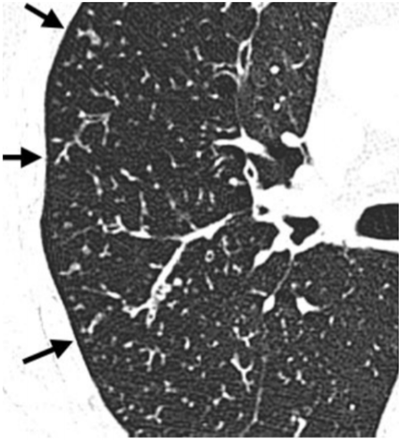

O padrão apontado pelas setas pretas na imagem de tomografia computadorizada (sem contraste venoso) abaixo é comumente observado em bronquiolite infamatória, inclusive infecciosa, como em casos de disseminação endobrônquica de micobacterioses.

Assinale a alternativa correta, que contém o padrão representado acima.